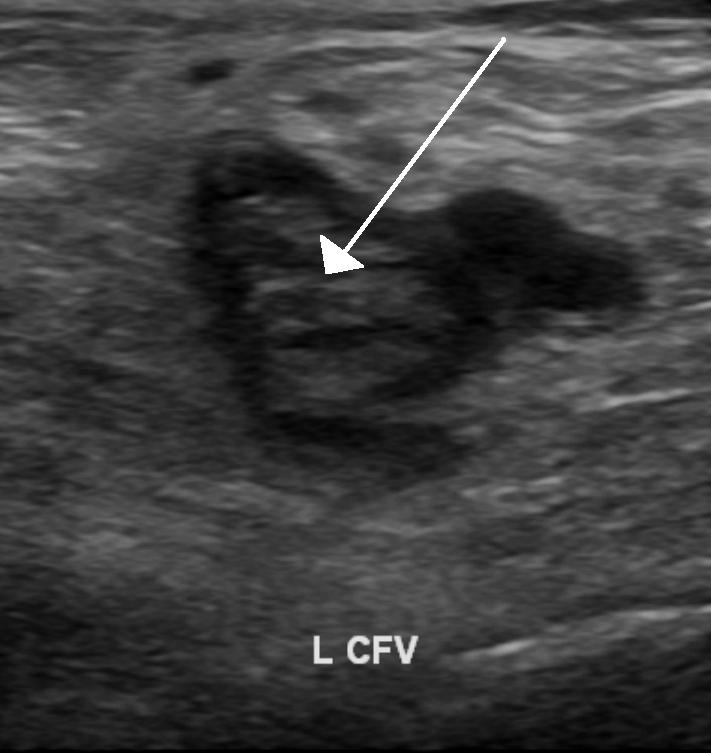

Ultrasonografi

Ultrasonografi vücuda gönderilen ve vücuttan dokuların anatomik yapısına göre farklı yansıyan yüksek frekanslı ses dalgalarının görüntüye dönüştüğü bir sistemdir. Doppler ultrasonografi (Doppler US) ise dokudaki artan damarlanma ve perfüzyonu kalitatif ve kantitatif olarak belirler.

USG kas, tendon ve bağ yaralanmalarının tanısında, yumuşak doku

kitlelerinin tespitinde ve biyopsi uygulamalarında kullanılır.